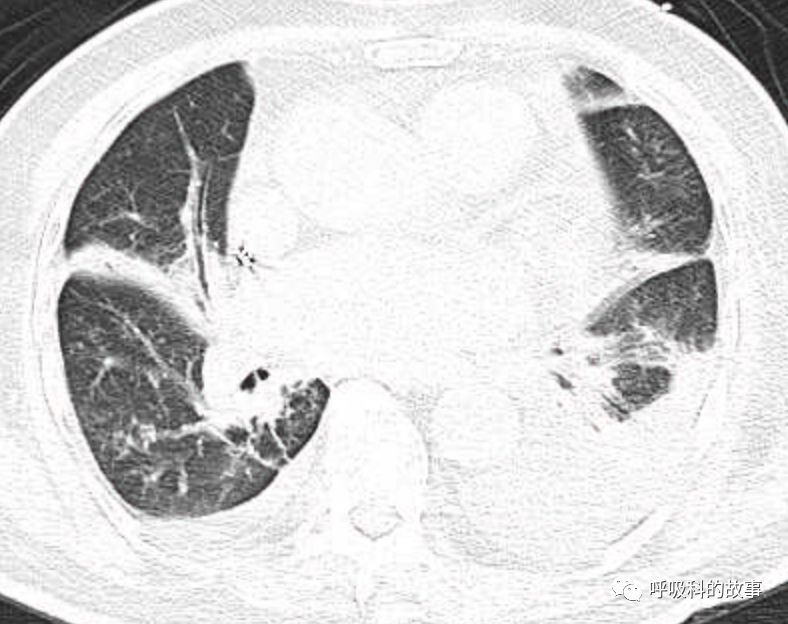

肺部CT如下:

以上的CT给我第一眼的感觉是肺炎,再结合患者有发热和血炎症指标明显增高,肺炎的诊断应该没有问题,但是胸水又是漏出液,结合脑钠肽增高和患者有胸闷气急的症状,心功能不全的诊断也能成立。在某些层面,肺部实变影以内中带为主,还要考虑肺水肿的诊断。入院后给予患者美罗培南抗感染、托拉塞米利尿治疗,以及化痰、雾化处理,患者体温在入院后三天就正常了,入院第五天复查NT-proBNP3390pg/ml;血常规示白细胞 13.5*10^9/L,中性粒细胞81.8%,淋巴细胞13.2%,超敏C-反应蛋白 25mg/L;电解质示钠 160mmol/L,氯 111mmol/L 。虽然炎症指标和心功能指标均有好转,但患者却仍旧精神差,每次查房时仍然表现嗜睡状,家属也反映患者不论白天还是夜晚多数时间不是太清醒。那么问题出在哪里呢?